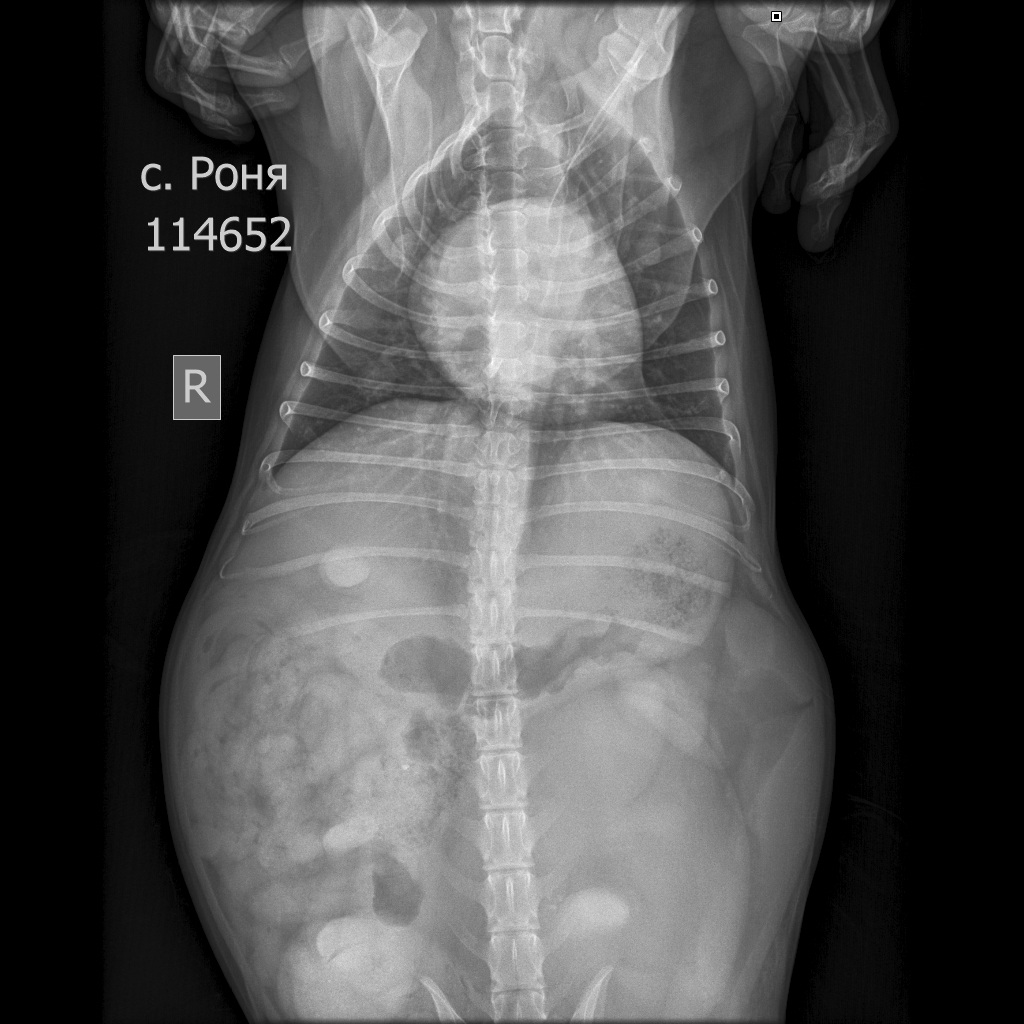

Рентген в двух проекциях и бак посев из раны